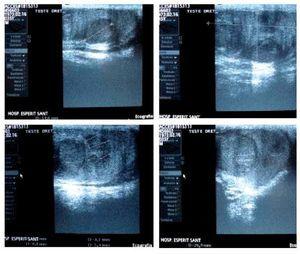

L'ecografia testicular (fig. 1) s'informava com a tumor testicular dret heterogeni amb la presència d'almenys 12 nòduls de diferents ecogenicitats i de mides, el més gran dels quals era de 16 mm, amb un patró de vascularització predominant perinodular, mentre que l'ecografia abdominal i la TC toraco-abdominal no presentaven alteracions significatives.

Figura 1 Tumor testicular dret heterogeni amb la presència d'almenys 12 nòduls de diferents ecogenicitats i mesures, el més gran dels quals era de 16 mm, amb un patró de vascularització predominant perinodular.